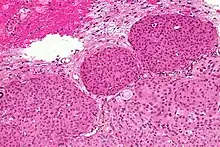

Histologically, meningioma cells are relatively uniform, with a tendency to encircle one another, forming whorls and psammoma bodies (laminated calcific concretions).[15] As such, they also have a tendency to calcify and are highly vascularized.